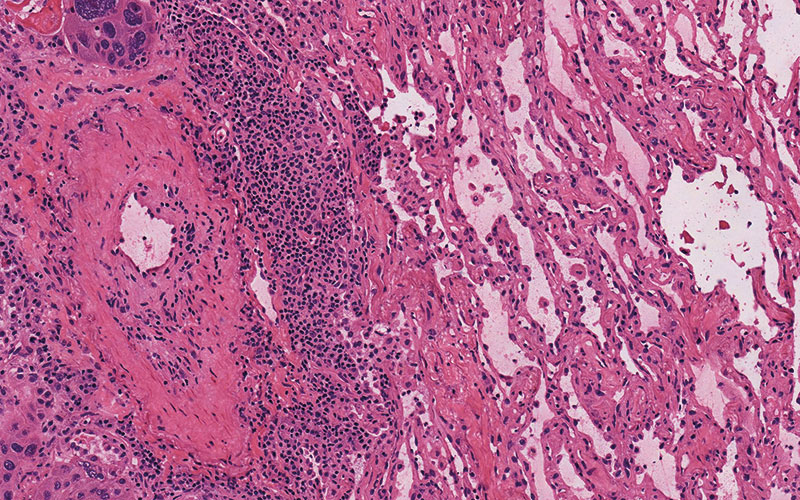

High Quality Results

Pathologists rely heavily on the frozen section technique for intra-operative consultation when the surgeon requires a rapid diagnosis or immediate feedback regarding surgical margins. Frozen sections offer a short turnaround time (15-20 minutes) but usually have the disadvantage of lower diagnostic quality than paraffin sections due to cryoembedding artifacts and variability in staining protocols.

Milestone offers a new approach to overcome these limitations by combining the artifact-free freezing process of PrestoCHILL with the superior processing and staining capabilities of PRESTO PRO.

The advantage of PRESTO PRO is that it provides a standardized and reproducible process that is capable of both efficient processing and staining protocols. This results in improved morphology of the analyzed specimens and maintains a high standard of result quality.